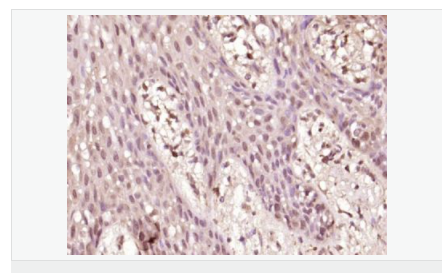

image.png